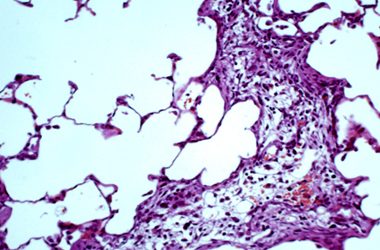

Els pulmons tenen una particularitat que comparteixen amb pocs òrgans: estan en contacte amb...

Estem fent recerca amb l'objectiu de curar una malaltia: la fibrosi pulmonar. Podreu anar seguint...